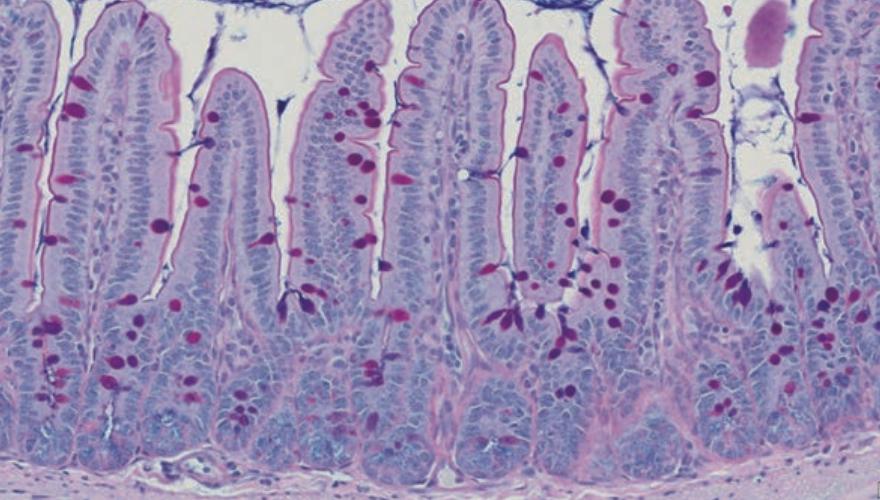

图.结肠炎小鼠在经抗炎细菌处理后的结肠杯状细胞变化。